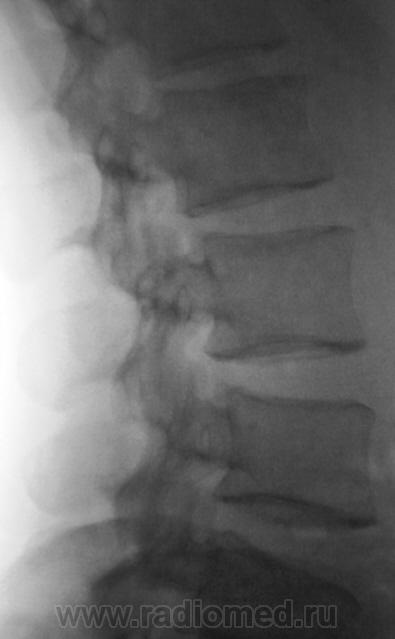

Пациент с болями в пояснице, направлен на рентгенологическое исследование поясничного отдела позвоночника.

задний спондилолистез L3,L4. сакрализация L5.признаки остеохондроза.аномалия тропизма L3-L4 справа ,L5 с обеих сторон.

При всем уважении к коллеге stovbav, лестничный микроретролистез L-2-L-3-L-4 может инициировать такие боли в спмне, что "мама, не горюй". А удлинение задне-нижних углов тел L-3,L -4 запросто могут оказаться косвенными признаками дорсальных протрузий диска..

Андрей Юрьевич, так никто и не спорит, только, как мне кажется, основной причиной в этом случае болевых проявлений будет не сколько микролистез, сколько микроподвывихи в дугоотростчастых суставах, но их то мы и не увидим на этих рентгенограммах. касаемо протрузии...тоже вряд ли ее степень столь значительна. Но ...без МРТ не разберемся...Улыбаюсь....

А позвонков разве не 6? И подготовить бы больного. У нас в поликлинике, почемуто не принято готовить больных к съёмке ПКОП,  только если к ЭУ.

Самый начальный деформирующий спондилоз. Листеза нет. Справа несколько небольших теней, могущих быть кокрементами в мочевых путях...